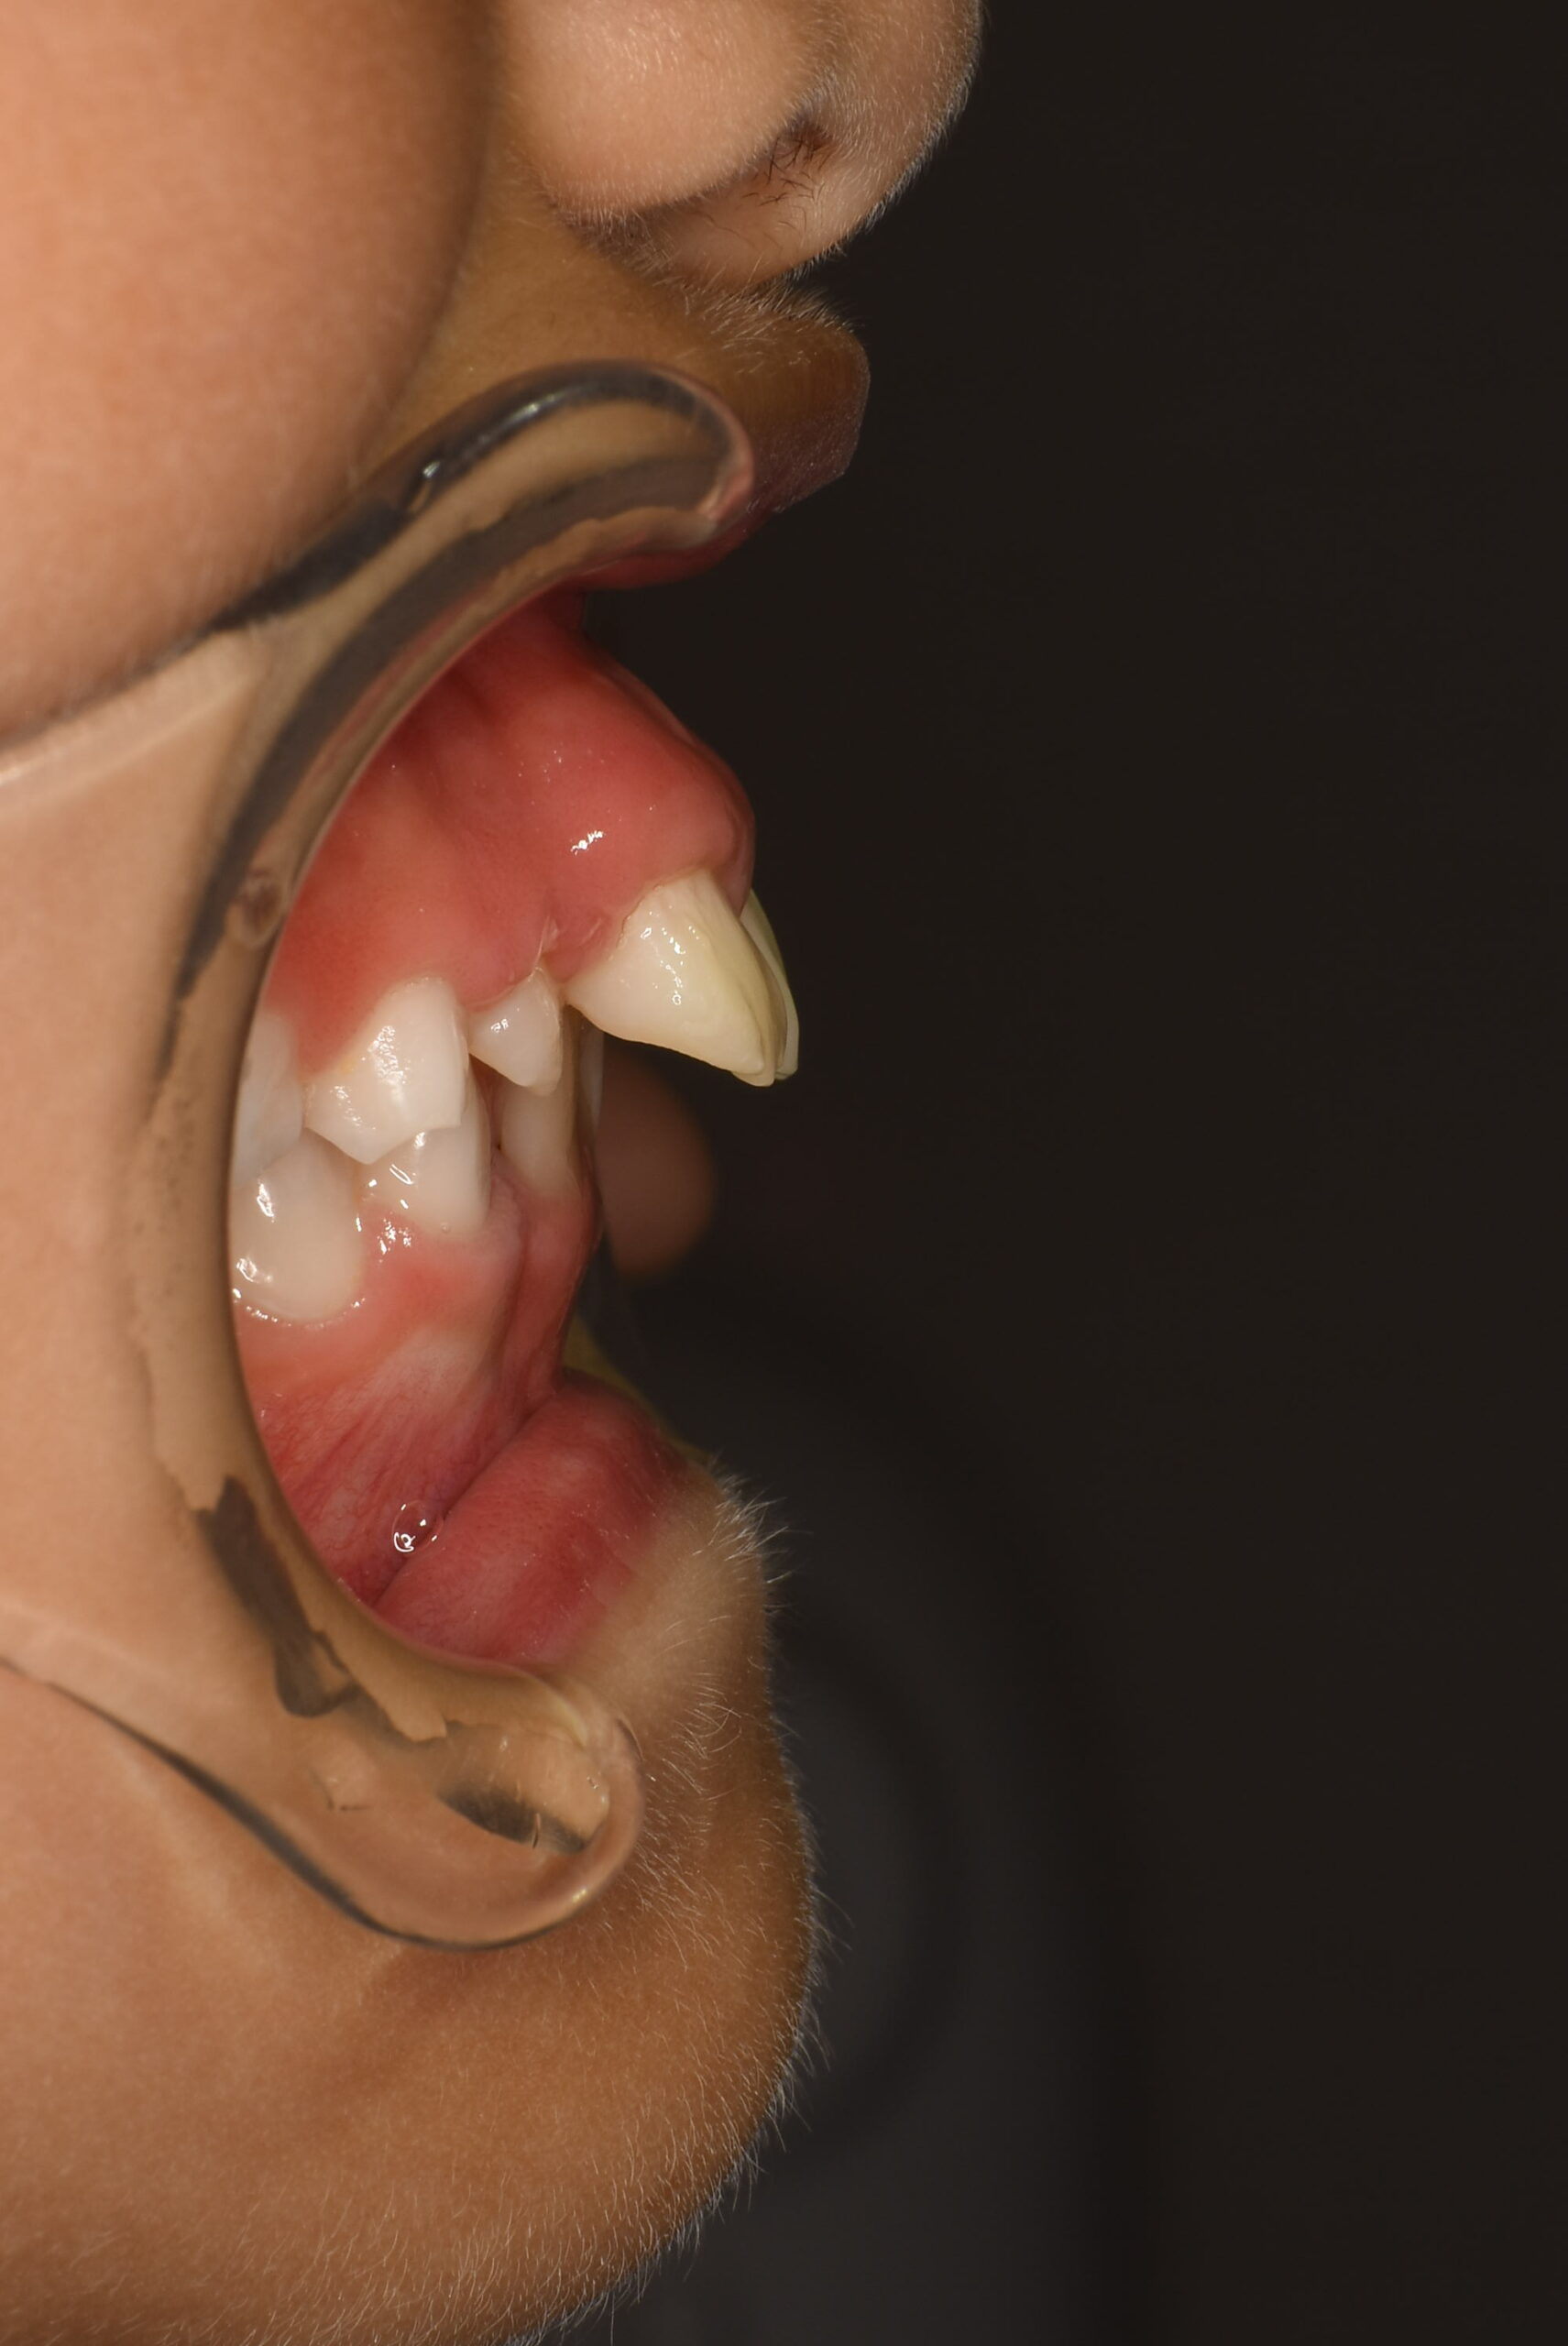

| 主訴 | 出っ歯 |

|---|---|

| 年齢・性別 | 女児・10歳(小学4年生) |

| 診断名 | 上顎前突(出っ歯)、口呼吸および舌の癖 |

| 治療内容 | 日中1時間と就寝時のマウスピース装着に加え、呼吸・舌・飲み込み・唇を鍛えるトレーニング(アクティビティ)を毎日実施。 |

| 治療期間 | 2年2か月(現在も継続中) |

| 費用(税込) | 583,000円 ※検査代・装置代・月1回調整料5,500円含む |

| リスク・副作用 |

|

| 備考 | 本症例は治療途中の経過写真です。治療結果には個人差があります。 |